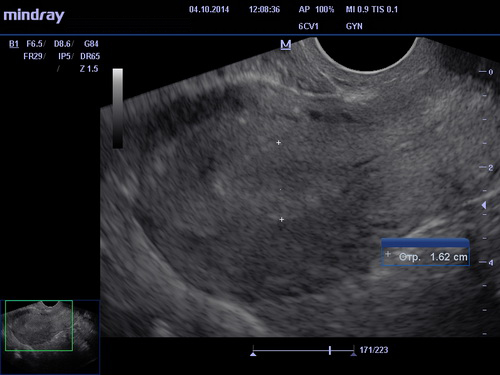

Что позволяет диагностировать УЗИ шейки матки

Большинство гинекологических заболеваний схожи по симптоматике и локализации болевого синдрома, УЗИ шейки матки позволит дифференцировать патологию и установить точный диагноз. Что в свою очередь играет важную роль при выборе методики лечения. Благодаря ультразвуку можно сделать квалифицированные выводы о состоянии женских половых органов, определить развывшиеся в них патологические процессы и степень их сложности. УЗИ матки позволяет диагностировать следующие болезни:

- миома матки – новообразование, имеющее доброкачественное течение, характеризующееся поражением миометрия. Проявляется болезнь рядом определенных симптомов: нарушение менструального цикла (преимущественно увеличение промежутка), кровотечение, наблюдающиеся в середине цикла, боли и неприятные ощущения внизу живота, частое мочеиспускание. УЗИ позволяет обнаружить миому, ее место расположения и степень развития заболевания, даже если ее размеры не превышают 1 сантиметр. При данной патологии матка пациентки будет увеличена;

- полипы эндометрия, то есть патологический рост слизистой оболочки. Характерной особенностью данного заболевания является то, что порой оно может протекать совершенно без симптомов, вызывая при этом бесплодие. УЗИ шейки матки показывает полип, образовавшийся на слизистой;

- рак шейки матки – это образование злокачественной опухоли, не имеющей точных очертаний и границ. Ультразвуковая диагностика позволяет определить наличие рака еще на его ранних стадиях, что дает возможность своевременно назначить квалифицированное лечение и в итоге побороть данный недуг. УЗИ шейки матки дает точную картину того, где расположена опухоль, ее форме и размерах;